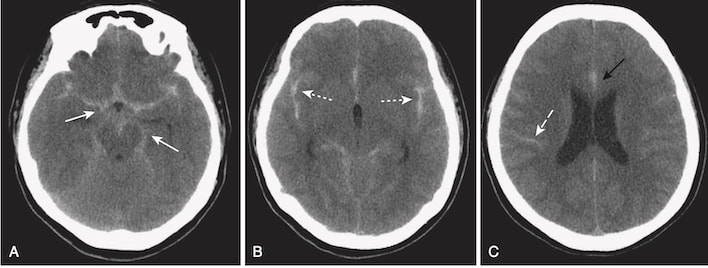

- Nhận biết đột quỵ do thiếu máu cục bộ (Hình 17):

- Trên CT, các phát hiện sẽ phụ thuộc vào khoảng thời gian đã trôi qua kể từ sự kiện ban đầu.

- 12 đến 24 giờ: Vùng suy giảm không phân biệt rõ trong một vùng phân bố mạch máu.

- > 24 giờ: Tổn thương có giới hạn biên rõ hơn với hiệu ứng choán chỗ đạt đỉnh điểm sau 3 đến 5 ngày và thường biến mất sau 2 đến 4 tuần (xem Hình 17, A).

- 72 giờ: Mặc dù thuốc cản quang hiếm khi được sử dụng trong trường hợp đột quỵ cấp, việc tăng cường độ tương phản thường xảy ra khi hiệu ứng choán chỗ giảm dần hoặc đã mất.

- > 4 tuần: Hiệu ứng choán chỗ biến mất; có một tổn thương giảm tín hiệu được giới hạn rõ khi chụp không cản quang (xem Hình 17, B).

A, Vào khoảng 24 giờ, tổn thương có viền bao quanh tương đối rõ (mũi tên màu trắng đặc) với hiệu ứng choán chỗ biểu hiện bằng sự đẩy lệch của não thất (mũi tên màu trắng chấm), đạt đỉnh điểm từ 3 đến 5 ngày và biến mất sau khoảng 2 đến 4 tuần.

B, Khi đột quỵ trưởng thành, nó mất hiệu ứng choán chỗ, có xu hướng trở thành một tổn thương giảm tín hiệu bờ thậm chí còn rõ nét hơn (mũi tên màu trắng đặc), và có thể kết hợp với giãn não thất kế cận (V) do mất chất não trong vùng bị nhồi máu.